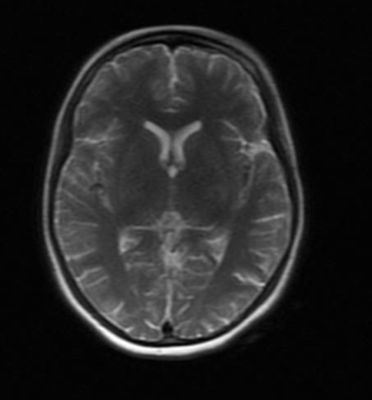

The patient’s imaging diagnostics were significant for a head CT that showed high-density foci in the globi pallidi, right greater than left, likely reflecting calcification (Figure 1) and a brain MRI completed on initial admission in late March that was significant for grossly abnormal subcortical enhancement with associated T2/Flair hyperintensity noted in the bilateral medial thalami, posterior putamen, midbrain, substantia nigra, and periaqueductal gray matter (Figure 2). On initial admission, clinicians performed an EKG, which was significant for diffuse T-wave inversions in the inferior and precordial leads (e.g. cerebral T-waves) that resolved on repeat testing (Figure 3).

Figure 2. MRI Brain (with and w/o contrast) on day of initial admission before treatment. MRI Brain showing symmetric restricted diffusion with associated T2/FLAIR hyperintensity noted in bilateral medial thalami, posterior putamen, midbrain (including the substantia nigra) and periaqueductal gray. Additional subtle T2/FLAIR hyperintensity without corresponding restricted diffusion noted dorsal medulla. No associated enhancement.